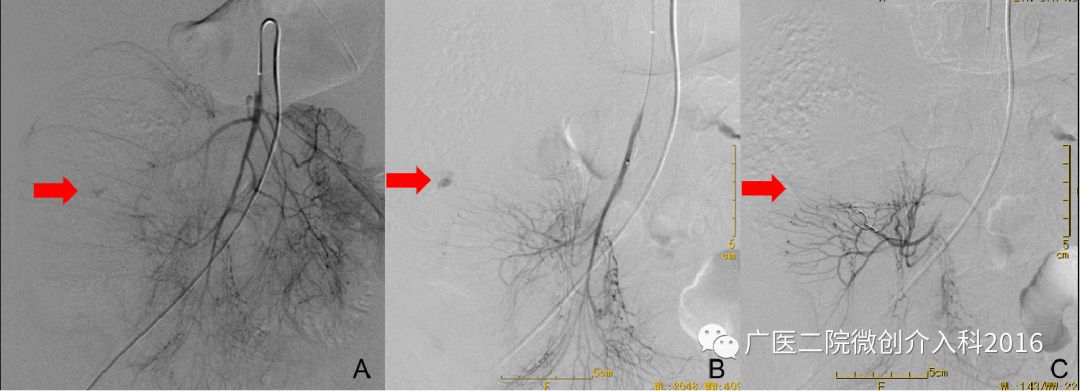

患者不明原因消化道出血,经内科药物治疗无效。图A、B行肠系膜上动脉造影显示造影剂外渗,明确诊断为升结肠出血,出血血管为右结肠动脉。经微导管注入弹簧圈栓塞出血动脉,图C再次造影示原出血征象消失。术后观察3天,患者出血停止,已无血便。

患者持续排血便3天,肠镜未能找到明确出血点。图A行肠系膜上动脉造影显示造影剂浓聚、外渗,明确诊断为回盲部肠道出血,出血血管为回结肠动脉。经微导管注入弹簧圈栓塞出血动脉,图B再次造影示原出血征象消失,患者出血停止。